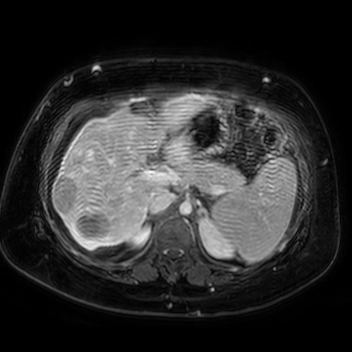

69 M with PMH of HCV cirrhosis & HCC s/p resection in 14 years ago presenting today for a screening ultrasound.

135/73 mmHg / 78 bpm / 16 breaths/min / 96.4°F

sclerae anicteric, no jaundice

CMP wnl, AFP 5